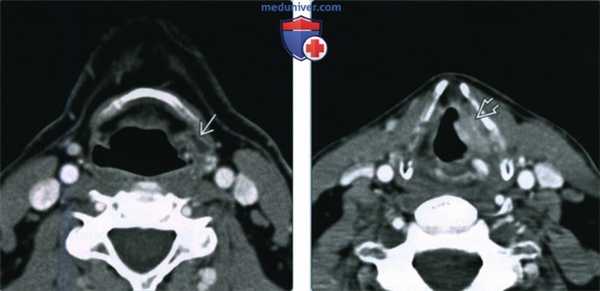

(Слева) При аксиальной КТ с КУ визуализируется небольшое вторичное внутреннее ларингоцеле в краниальных отделах окологортанного пространства слева.

(Справа) При аксиальной КТ с КУ на уровне голосовых связок визуализируется инфильтративное объемное образование (ПКР) левой голосовой связки, накапливающее контраст. При эндоскопическом исследовании было обнаружено распространение опухоли на ложную голосовую складку, лежащую выше. При КТ были выявлены признаки местного объемного воздействия, обусловленного вторичным внутренним ларингоцеле.